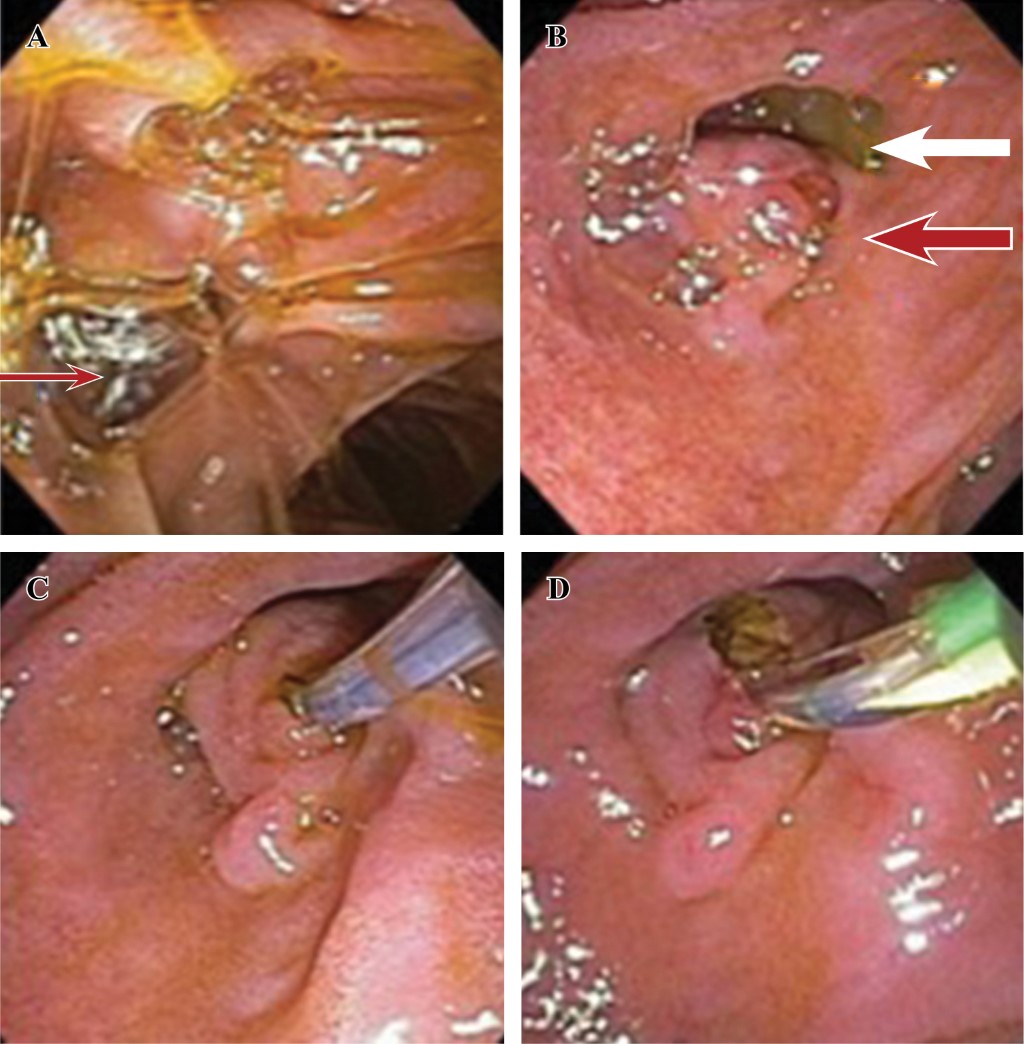

Se realiza esfinterotomía completa con abundante salida de bilis, sin detritus, se realizan dos barridos con balón extractor sin observar salida de litos y se coloca prótesis plástica tipo Amsterdam.

Después del procedimiento, el paciente evoluciona de manera favorable con normalización de la biometría hemática y pruebas de función hepática (Figura 3).

En este caso el tratamiento endoscópico consistió en esfinterotomía y asegurar el drenaje biliar con endoprótesis, ya que por el divertículo yuxtapapilar aumenta el riesgo de presentar pancreatitis de repetición.

Figura 3